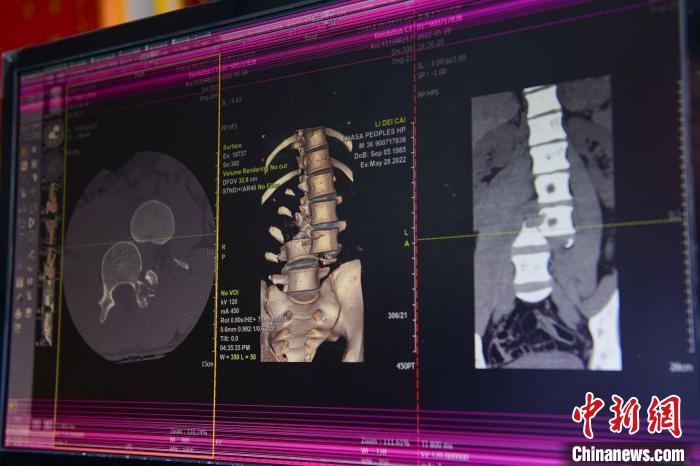

圖為患者術(shù)前,腰3/4脊柱骨折伴脫位?!≡髑?攝

通道開通后,拉薩市人民醫(yī)院完成了兩例脊柱創(chuàng)傷截癱患者的救治。一例23歲的病患為胸12椎體爆裂骨折伴截癱,另一例36歲的病患腰椎體骨折脫位伴雙下肢癱。按照脊髓損傷救治綠色通道流程,術(shù)前充分快速完善相關(guān)檢查,充分術(shù)前評(píng)估,向患者詳細(xì)交代手術(shù)風(fēng)險(xiǎn),入院當(dāng)天急診行手術(shù)治療。

北京“組團(tuán)式”醫(yī)療援藏專家、主治醫(yī)師何蔚介紹,兩名患者屬于脊柱骨折合并雙下肢截癱,手術(shù)十分復(fù)雜,需要快速且安全的完成手術(shù),在脊柱外科手術(shù)中屬于四級(jí)手術(shù),難度最高的一種。